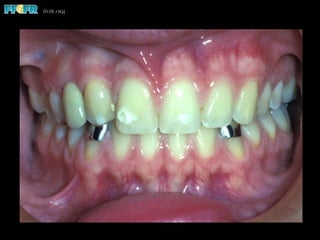

Affect of Incisally

Positioned Gingiva

Produces Short

Clinical Crowns

RBP Abutment Tooth Discoloration

(Evaluated in 7 Studies)

•  62 of 343 prostheses affected

•  Mean of 18%

•  Range from 3 to 37%

•  Increases with time